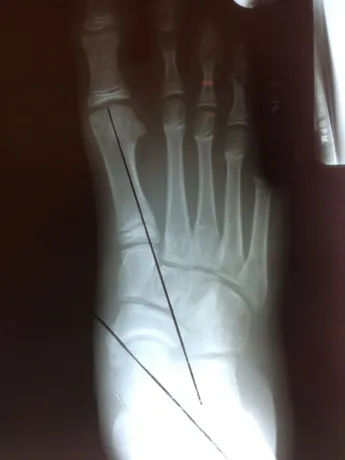

Pre and Postop X-rays Subtalar Joint Implant (Below)

Patient JD